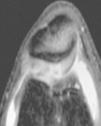

Figura 3 RM. Imatge potenciada en T2 amb supressió de greix. Lesió condral àmplia en ròtula, faceta externa i cresta condral.

L'RM mostra (figs. 1, 3 i 5):

• Múltiples cossos lliures intraarticulars.

• Lesió condral àmplia en faceta externa i cresta de ròtula, de gruix parcial.

• Vessament articular.

• Lligaments i meniscos i resta d'estructures íntegres.